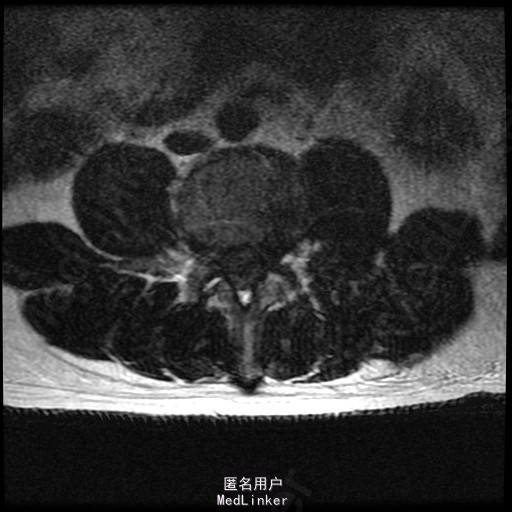

查体:腰部叩痛,腰部活动受限,左侧膝内侧、小腿外侧、内踝、足部感觉减退,右侧小腿、足背感觉减退,屈髋、伸膝、踝背伸肌肌力左侧4级,右侧4-5级,踇背伸、跖屈肌肌力左侧3-4级,右侧4级,双侧膝腱反射+,跟腱反射+,双侧巴氏征阴性,直腿抬高试验左侧40°阳性,右侧阴性。 辅助检查: X-ray:腰椎退行性变,多节段不稳 CT:腰椎间盘突出并椎管狭窄伴钙化,腰2-3,3-4,4-5,腰5骶1 MR:腰椎间盘突出并椎管狭窄,腰2-3,3-4,4-5,腰5骶1 上传受限无法全部上传,见谅

诊断:腰椎间盘突出症并椎管狭窄 处理: 1、完善相关辅助检查,明确诊断,有无手术指证; 2、完善手术评估,有无手术禁忌,手术风险及并发症; 3、在全麻下行腰椎后路多节段减压椎间植骨融合内固定术 4、腰2-3,腰3-4行开窗减压,腰4-5,腰5-骶1行椎间Cage植骨融合